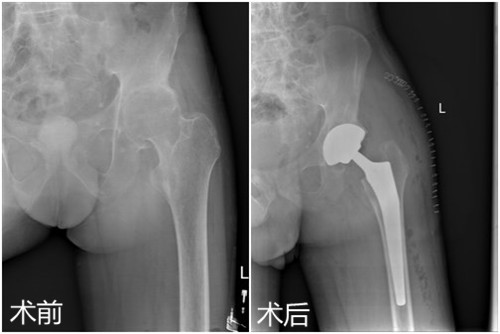

临床医学院/附属医院为强直性脊柱炎患者成功实施全髋关节置换术

日前,临床医学院/附属医院骨三科为一名35岁强直性脊柱炎累及双侧髋关节男性患者施行了左侧人工全髋关节置换术,术后恢复良好,目前患者已经可以下地行走。该例手术的成功标志着该院骨科在复杂髋关节置换领域的技术日臻完善。

患者田先生,35岁,因身患强直性脊柱炎累及双侧髋关节,行走呈跛行步态,颈部、腰部呈僵直状,只能拄拐行走。两年前,他逐渐出现髋部疼痛不适症状,起初自行在家休息后症状稍有缓解,但两年来上述症状反复出现,并于两个月前明显加重,失去了左侧的行走能力,在当地医院就诊后效果欠佳,慕名来临床医学院/附属医院就诊。临床医学院/附属医院影像学检查显示:左髋股骨头缺血坏死继发关节退变。骨三科朱述浪主任在邀请风湿免疫科专家会诊和多次全科讨论后,决定为患者实施左侧人工全髋置换术,并制定详细的手术方案。手术过程顺利,术后切口愈合良好,术后医护人员对其进行了专业的康复锻炼,患者出院时双侧髋关节屈曲活动度超过80度。患者对临床医学院/附属医院的医疗技术及优质的护理服务予以高度赞扬。

据朱主任介绍,强直性脊柱炎是一种慢性进行性炎性疾病,因初始症状较轻,多被患者所忽略,且早期易于类风湿关节炎混淆,待发展为晚期时大关节可发生畸形和强直,病人多丧失行走能力,形同瘫痪,生活难以自理,给患者及家属带来灾难性的结果。朱主任建议,目前人工髋关节的材料与人体相容性好,设计符合生物力学,可以用30—40年,适合活动较多的年轻人,这类患者应尽早考虑髋关节置换手术治疗,其间生活能恢复自理,生活质量提高,能够大大减轻患者及家庭的负担。